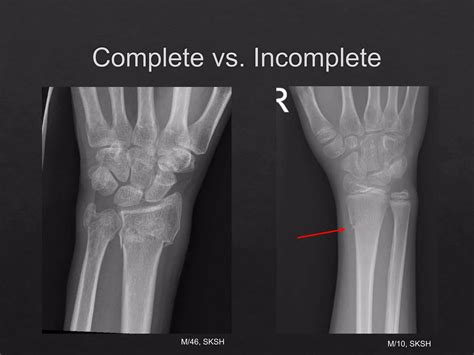

Navicular fracture causes, symptoms, diagnosis, treatment & prognosis